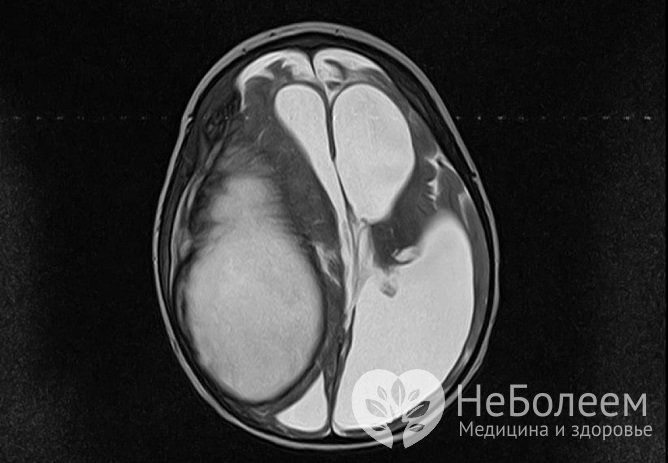

Абсцесс головного мозга – это локальное образование инфекционной природы, представляющее собой скопление гноя, изолированного от здоровых тканей мозга твердой соединительно-тканной капсулой. Составляет не более 1-2% от всех внутричерепных образований. Может встречаться в любом возрасте, но наиболее часто возникает у людей за 40. Болеют чаще мужчины.

Окончательное формирование капсулы и постепенный регресс признаков воспаления. К этому моменту абсцесс имеет полностью сформированный вид (слои представлены изнутри наружу): некротический центр, периферическая зона воспалительных клеток и фибробластов, коллагеновая капсула, новая сосудистая сеть, область реактивного глиоза с отеком. |